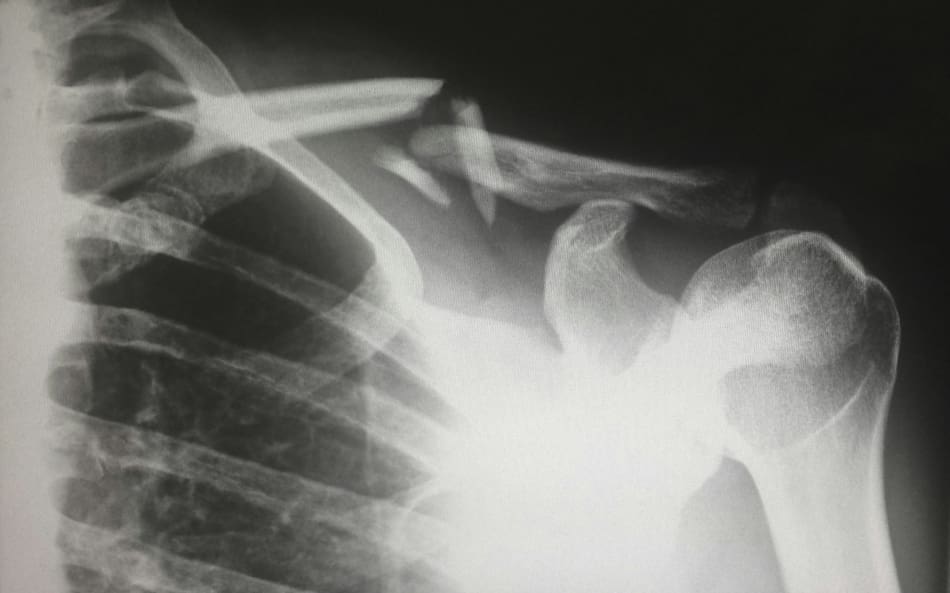

Hueso roto, radiografía. Foto: Unsplash